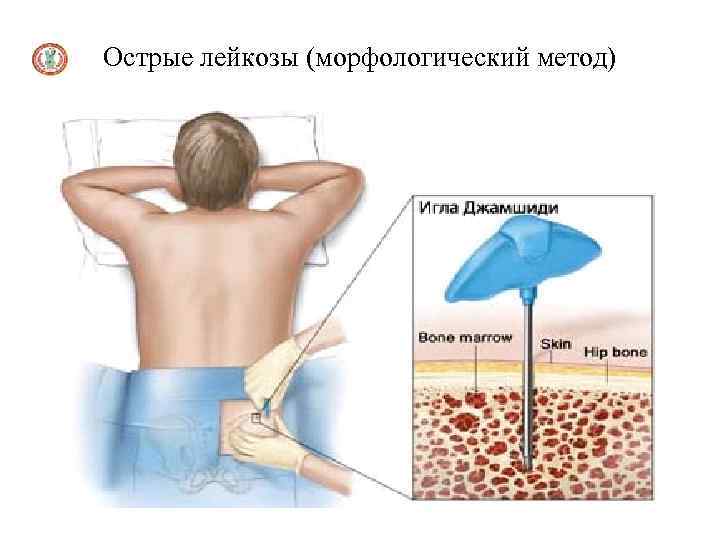

Острые лейкозы (морфологический метод)

Диагностика острых лейкозов Миелограмма (количественное определение всех клеточных форм костного мозга) получается при стернальной пункции или трепанобиопсии подвздошной кости: увеличение содержания бластных клеток от 20% и до тотального бластоза. Морфология бластов различна в зависимости от типа лейкоза. Отмечается увеличение промежуточных форм, лимфоцитоз, красный росток кроветворения угнетён (за исключением острого эритромиелоза), мегакариоциты отсутствуют или их количество незначительно (за исключением острого мегакариобластного лейкоза)